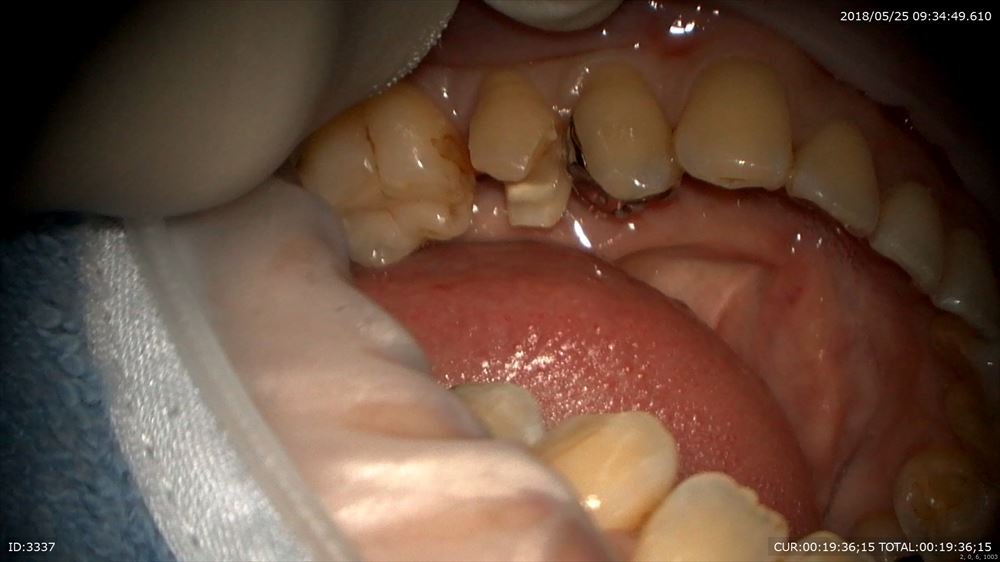

今日の修復。左下5番の修復。前回神経を保護したケース。

調整